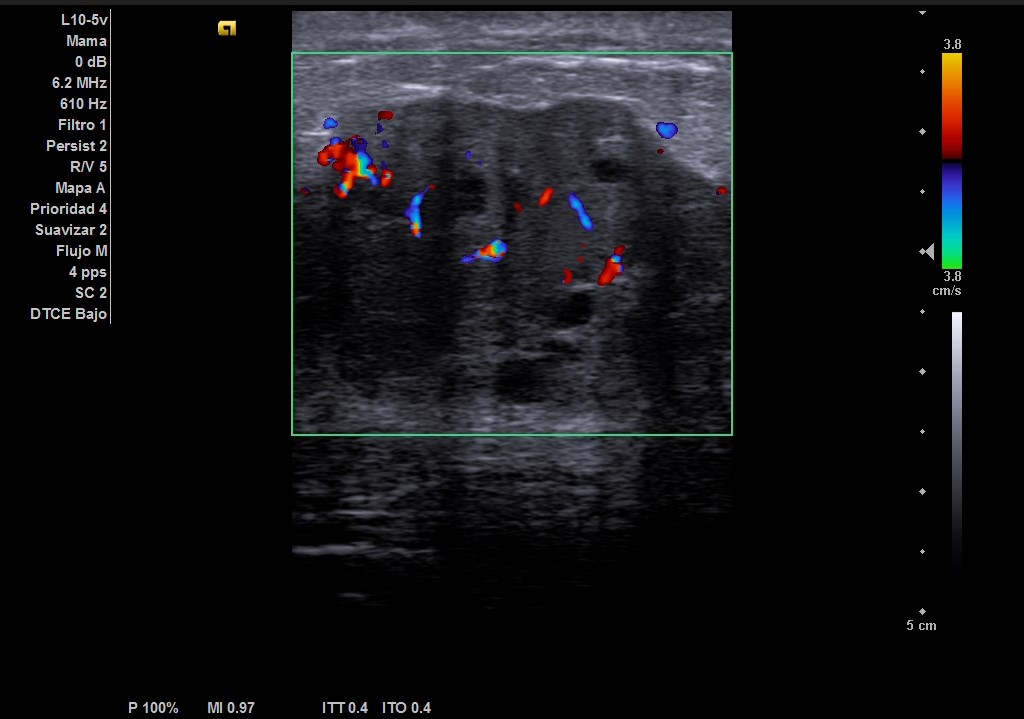

Hallazgos ecográficos

Ecografía: mama izquierda se observa tumoración hipoecogénica lobulada en cuadrante superior externo de aproximadamente 4 cm, heterogénea, que capta al Doppler color y dos adenopatías de aspecto reactivo en axila homolateral. Imagen sospechosa de malignidad.